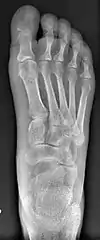

Bunion (hallux valgus) deformity is actually part of a complex of anatomical derangements of protruding mass (bunion), buckling of big toe (hallux valgus) and the bone behind it (metatarsus primus varus), displaced sesamoid bones (detrimental to the important walking function of big toe), collapsed metatarsal arch and several other secondary changes that are the domino effects of metatarsal primus varus. Thus, metatarsus primus varus correction has become the primary objective of all bunion surgeries.

Primus varus deformity is the leaning of the first metatarsal bone away from the second metatarsal and towards the opposite foot (Fig. 1). As it leans over, its head sticks out to form the bunion bump and it also widens the forefoot to cause shoes feeling too tight. Thus when bunion pain becomes unmanageable, surgical correction is to narrow the forefoot by repositioning of the first metatarsal head back to its normal position. This can be done by osteotomy (bone-breaking), soft tissue (non-osteotomy) or fusion techniques.

Syndesmosis procedure addresses specifically the two fundamental problems of metatarsus primus varus deformity that gives rise to the bunion deformity. They are leaning and instability of the first metatarsal bone . Syndesmosis procedure uprights the leaning first metatarsal bone with strong binding sutures between it and the second metatarsal bone (Fig. 2) and then also stabilizes it uniquely by creating a fibrous connecting bridge between these two bones (Fig. 3, 4). First metatarsal bone can be readily realigned because by definition of the metatarsus primus varus deformity its first metatarsal is abnormally loose and mobile.